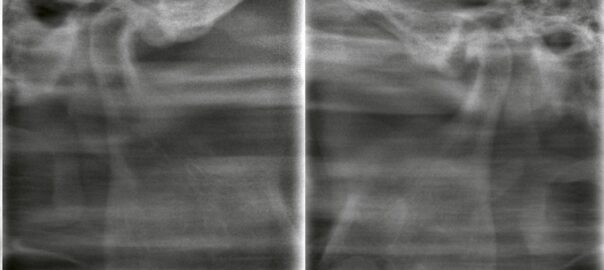

矯正治療に伴う第一小臼歯抜歯|CTで左右差を見極めた症例

こんにちは。東京都中央区銀座5丁目にある 【親知らず・顎関節症クリニック銀座(通称:オヤアゴクリニック)】です。 当院は以下の3つに特化した歯科クリニックです。 * 親知らずの抜歯 * 顎関節症の治療 * アスリートのた … 続きを読む 矯正治療に伴う第一小臼歯抜歯|CTで左右差を見極めた症例